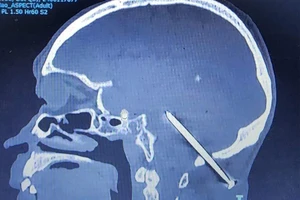

Bị cây đinh đâm vào não suốt 1 năm mà không biết